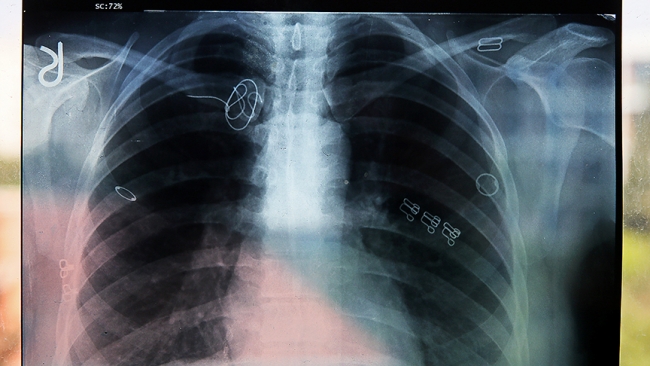

Adli Tıp Kurumunca hazırlanan raporda, ameliyatın ardından davacının vücudunda kalan "CVP kateter kılavuz teli"nin ömür boyu kullanılacak kan sulandırıcı ilaçlarla hayati tehlike oluşturmayacağı belirtilerek, benzeri cihaz parçalarının yıllarca bu şekilde damarda kaldığı, bu tür durumlarda yeni bir cerrahi müdahalenin hastaya bırakılması gerektiği ifade edildi.

Raporda, bunun davacıdaki gibi riskli durum oluşturmadığı ve ilaç kullanılarak risksiz şekilde tedavi edilebileceği kaydedilerek, sağlık personeline atfedilecek kusur bulunmadığı açıklandı.